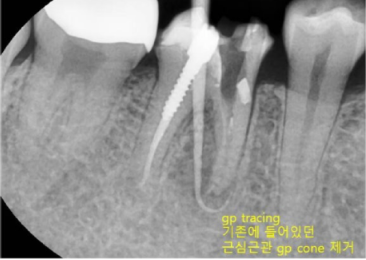

수많은 임플란트 케이스를 진행하면서도 이백점치과는 '자연치아는 그 어떤 임플란트로도 대체할 수 없다'는 확고한 철학을 가지고 있습니다. 그래서 언제나 자연치아를 살리기 위해 최선을 다합니다. 이번 사례는 타 치과에서 발치 진단을 받은 치아를 성공적으로 재신경치료하여 살려낸 고난도 케이스입니다. CASE. "뽑아야 한다던 치아, 재신경치료로 살려냈어요!" ○환자분의 고민 - 타 치과에서 이미 신경치료를 받았음에도 계속 불편감을 호소하며 내원한 환자분이었습니다. - 오른쪽 아래 치아 앞 잇몸에 고름 주머니(농양)가 생겨 있었고, 방사선 사진상 뿌리 끝에 심한 염증과 고름이 확인되었습니다. - 더욱이 이미 신경치료 후 포스트(기둥)까지 박혀있어, 타 치과에서는 이미 '발치'를 고지받은 상황이었습니다. ![]() ○ 진단: 정밀 CT 촬영을 통해 고름 주머니가 생긴 원인을 분석했습니다. 기존 신경치료가 되어있던 뒤쪽 뿌리가 아닌, 앞쪽 뿌리의 신경관에 문제가 발생하여 염증이 재발된 것을 정확히 진단했습니다. ![]() '발치 없이' 자연치아를 살리는 재신경치료 이백점치과는 고심 끝에 기존 기둥을 그대로 두고, 문제의 원인이었던 앞쪽 뿌리를 다시 신경치료하기로 결정했습니다. 1. 정교한 기존 재료 제거 : 기존에 충전되어 있던 신경치료 재료를 조심스럽게 제거했습니다. 2. 꼼꼼한 신경관 재정비 : 뿌리 끝까지 신경관을 깨끗하게 넓히고 소독했습니다. 3. 염증 해소 약재 적용 : 뿌리 끝 염증 해소를 위해 염증 완화 약재를 세심하게 적용했습니다. 기적 같은 결과, 1년 후에도 건강하게! - 3주 만의 드라마틱한 호전: 불과 3주 만에 바깥 잇몸의 고름 주머니가 완전히 없어졌고, 환자분의 모든 증상이 사라졌습니다. 이후 신경치료를 마무리하고 보철 치료까지 성공적으로 진행했습니다. - 1년 뒤에도 완벽한 경과: 1년 뒤 다시 체크했을 때, 염증은 전부 가라앉았고 고름 주머니 흔적 없이 깨끗했습니다. 심지어 염증으로 녹아있던 뼈 부위에는 새로운 뼈가 형성되고 있음이 확인되었습니다. ![]() 환자분 또한 통증 없이 건강하게 생활할 수 있어 매우 감사하다는 인사를 전했습니다. ![]() 이처럼 살리기 어렵다고 판단되던 고난도 치아를 발치 없이 살려낸 사례는 의료계 내부에서도 높은 평가를 받았습 니다. 이백점치과는 항상 환자분의 입장에서 생각하며 '발치만이 해답이 아님'을 증명하고, 자연치아 보존을 위한 최선의 노력을 다하고 있습니다. ![]() |